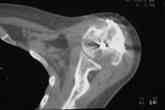

Анализ ситуации позволяет считать, что основными причинами контрактуры являются неправильная репозиция фрагментов головки (разворот кверху и кзади), асептический некроз головки плечевой кости (отчетливое склерозирование на СТ).

2. Сохранение металлоконструкции с удалением выступающих за пределы головки винтов, релиз сустава, заполнение дефекта (b5_ct.jpg) на стыке метафиза и головки аутотрансплантатом для устранения «триггера», ранняя реабилитация.